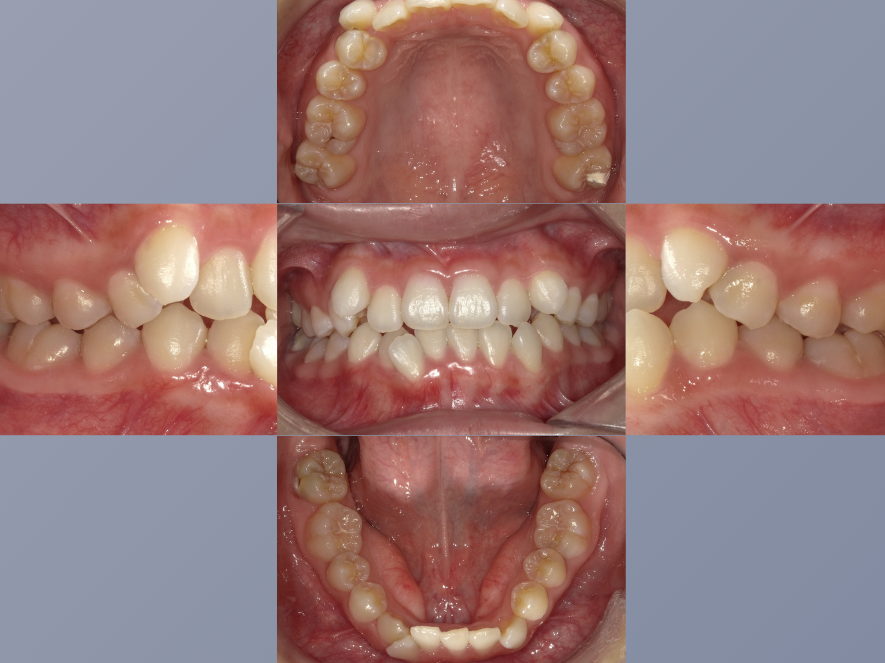

治療後

| 年齢・性別 | 20代・女性 |

|---|---|

| 主訴 | 歯並びが気になる。 |

| 期間 | 2年6カ月 |

| 費用 | 1,452,000円 |